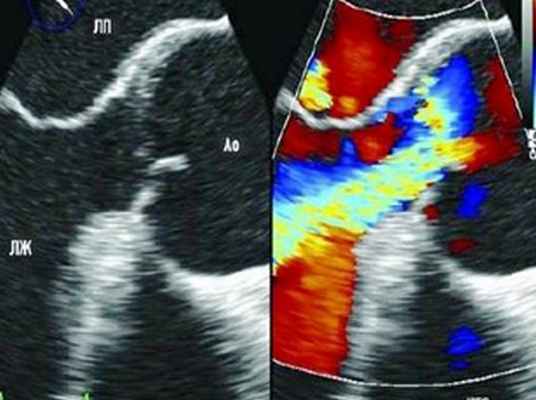

Расслоение начальных отделов аорты может быть определено при помощи трансторакальной или чреспищеводной ЭХО-КГ.

- Ультразвуковые методы исследования – при наличии аневризмы восходящего отдела аорты (I и II тип расслоения) или наличия пороков аортального клапана достаточно информативным методом диагностики является ЭХО-кардиография (УЗИ-сердца).

Если есть подозрение на расслоение аорты, используют различные методы визуализации. Например, чреспищеводная эхокардиография, представляющая собой УЗИ сердца, при котором ультразвуковой зонд вводится через пищевод. Эффективность данного исследования зависит от умений и опыта врача. К другим способам диагностики данного заболевания относится ультразвук, контрастная компьютерная томография (КТ) и магнитно-резонансная томография (МРТ).